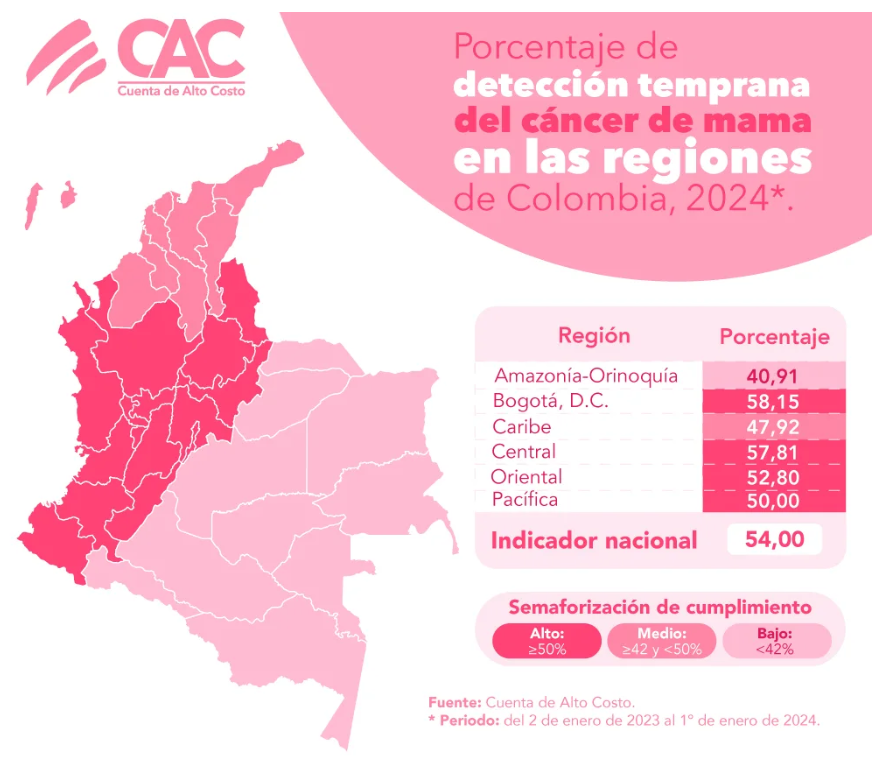

Progressi nella diagnosi precoce, ma con lacune regionali Nel suo bollettino ufficiale, l'High Cost Account ha evidenziato che la diagnosi precoce ha raggiunto una media nazionale del 54%. Tuttavia, le regioni Amazzonia-Orinoquia (40,91%) e Caraibi (47,92%) rimangono al di sotto dell'obiettivo fissato nel consenso nazionale del 2016.

Tasso di diagnosi precoce del cancro al seno, secondo l'High Cost Account. Foto: CAC.